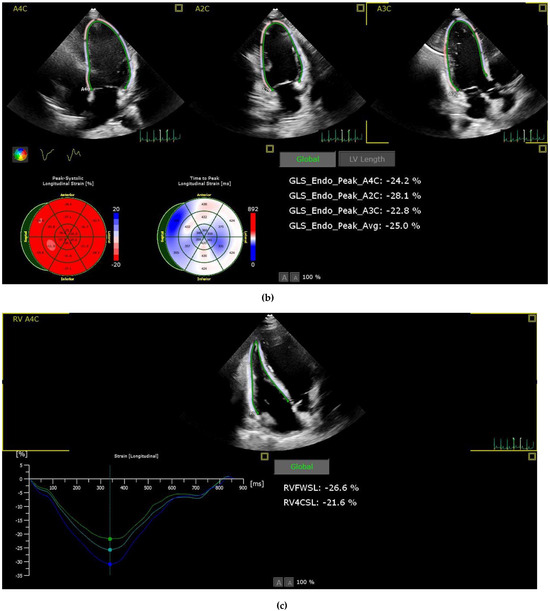

Patients with suboptimal image quality for strain analysis were excluded from the study. The echocardiographic images were analysed by a cardiologist who is particularly interested and trained in cardiovascular imaging and strain echocardiography. The strain values, including the right ventricle GLS (RVGLS) and right ventricle free wall strain (RV-FWSL), the LVGLS, and components of the LAS (atrial reservoir (LAS-r), conduit (LAS-cd), and contractile (LAS-ct) function), were examined from the stored echocardiographic images using a commercially available workstation (QLAB version 13) and by following the recommendations of the EACVI [13] (Figure 1).

Figure 1.

Imaging of STE components of left atrial (a), left ventricle (b) and right ventricle strain (c). Abbreviations: LA: Left atrium, A4C: Apikal four chamber, LASr: Left atrial reservoir strain, LAScd: left atrium conduit strain, LASct: left atrium contractile strain, A2C:Apikal two chamber, A3C:Apikal three chamber, GLS: Global longitudinal strain, Avg: Average, LV: Left ventricle, RVFWSL: Right ventricle free wall strain longitudinal, RV4CSL: Right ventricle four chamber strain longitudinal.